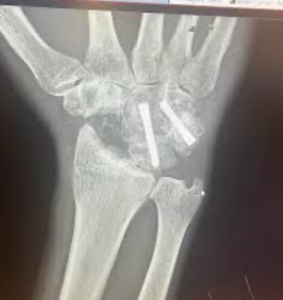

Wrist fusion surgery, or wrist arthrodesis, removes the remaining cartilage between selected wrist bones and fixes them together using plates, screws, or bone grafts. As healing occurs, the bones fuse into one solid bone, forming a stable and pain-free wrist. This surgical technique has been used for decades and remains one of the most reliable treatments for severe wrist arthritis, rheumatoid arthritis wrist conditions, and complex wrist injuries.

Wrist fusion surgery is performed under regional or general anesthesia. An incision is made over the dorsal aspect (back) of the wrist to expose the damaged joint. The remaining cartilage is removed from the surfaces of the wrist bones. In total wrist arthrodesis, the surgeon aligns the carpal bones, radius, and metacarpal bone in a functional position before securing them with a plate and screws.

In partial wrist fusion, only selected bones are fused together using specialized plates or compression screws. Bone grafts—often harvested from the iliac crest or distal radius—are placed between the prepared joint surfaces to promote fusion and healing. The hardware holds the bones in place while the fusion occurs over several weeks.